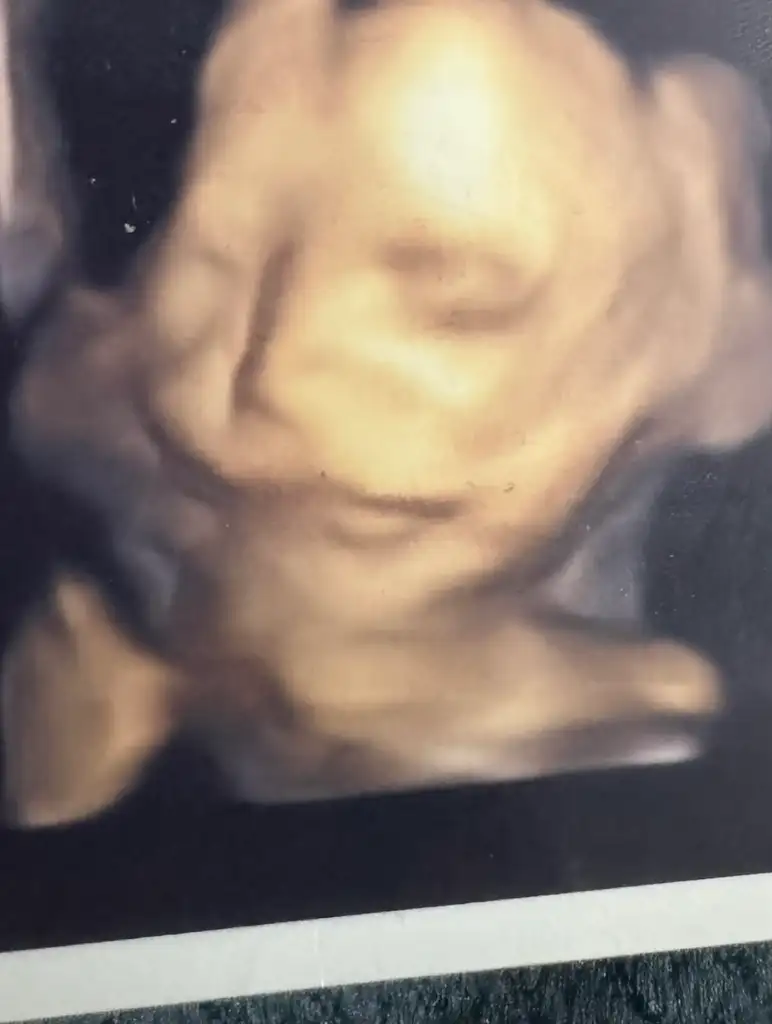

Oyyy maşallah yaaaTeyzeleri oğluma bakındudakları kalın mı bana mı öyle gelir Bana benziyor kızlar bu bebek gözleri de büyük sanki